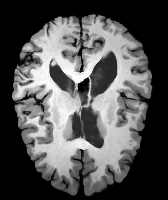

Results: All trained networks are evaluated using Dice overlap scores between predictions and the manual segmentations for the segmentation network, or between the warped moving segmentations and the target segmentations for the registration network. Tabs. 1 and 2 show results for the knee and brain MRI experiments respectively in Dice scores (%). Fig. 2 shows examples of knee MRI registrations and brain MRI segmentations.

Qualitative results: DA achieves more anatomically consistent registrations than the mono-networks on the knee (Fig. 2) and Brain MRI samples (see supplementary material).

Moving

Target

Mono-0

Mono-21

DA-1

DA-21

Mono-65

Image

Manual Seg

DA-1

Mono-5

DA-5

Mono-200